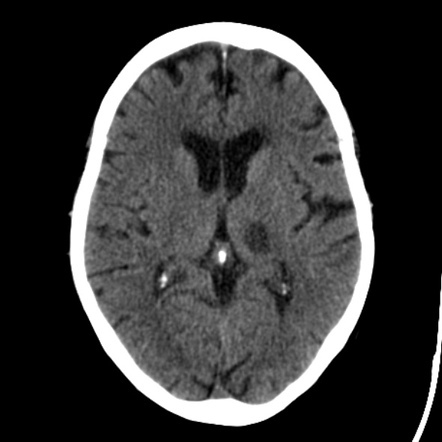

Comparison of ischaemic vs haemorrhagic stroke on CT scan

Haemorrhagic - white blood

Ischaemic = delayed response in brain